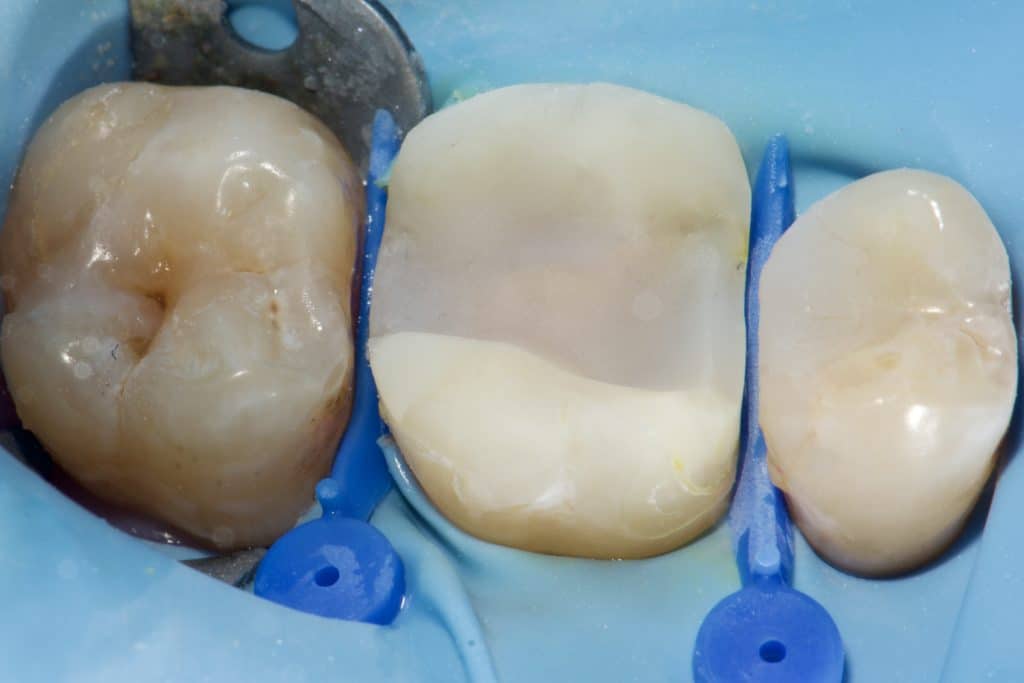

“Can a direct composite overlay function as effectively as an indirect lithium disilicate restoration? Composite restorations, once used as a long-term temporary solution for badly damaged molars, are now considered permanent. While the composite material remains the same, our understanding of its adhesive and physical properties has evolved. The procedure may be more time-consuming and require multiple stages in the same visit, depending entirely on the dentist’s skills.